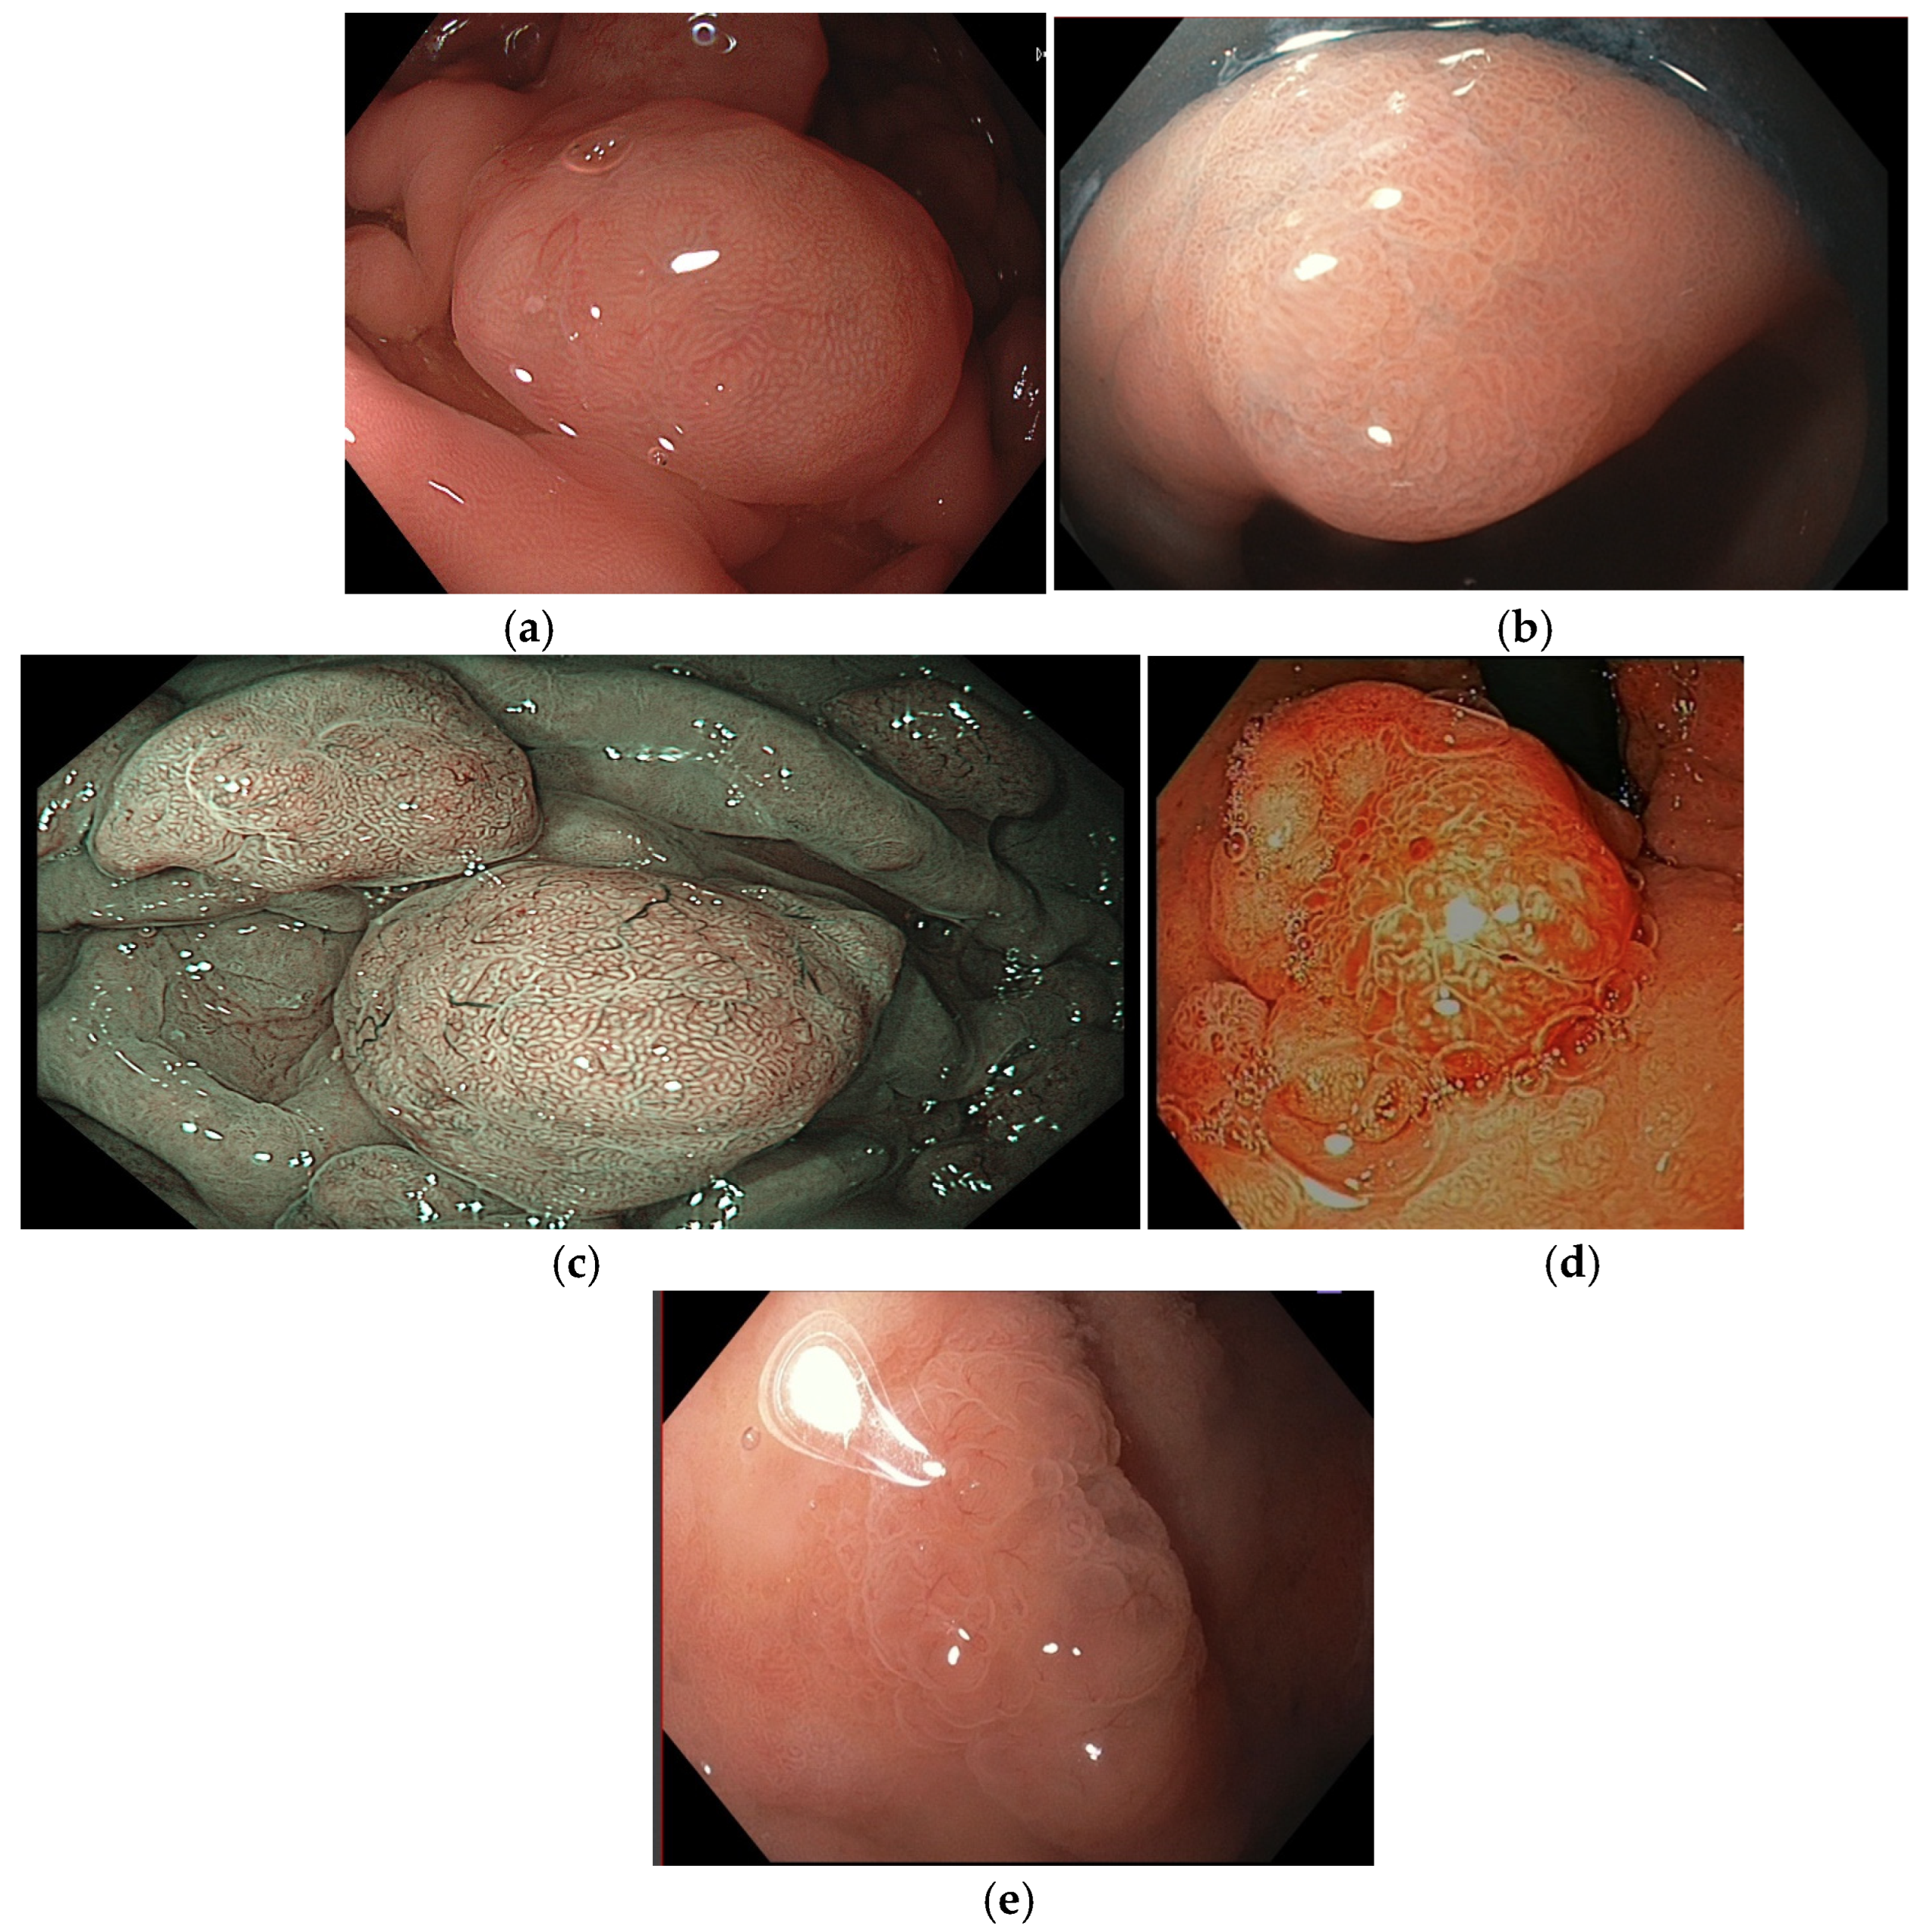

Figure 6. Mucosal and microvascular patterns. (a) Prolonged mucosal pattern; (b) villous mucosal pattern; (c) honeycomb microvascular pattern; (d) dense vascular pattern; and (e) core vascular pattern. Images were provided by Dr. Glòria Fernández-Esparrach (a,c,d) and Dr. Gonzalo Latorre (b,e).

Omori et al. classified gastric polypoid lesions by mucosal pattern into four categories (small round; prolonged; villous or ridge; unclear) and by microvascular patterns into five categories (honeycomb; dense vascular; fine network; core vascular; unclear) (Figure 6). In their analysis for predicting FGPs and GHPs, the most suggestive patterns were the combination of small round/honeycomb (sensitivity 94.7%; specificity 97.4%) and prolonged and villous or ridge/dense vascular patterns (sensitivity 93.6%; specificity 91.6%), respectively. Contrarily, the most favorable combined patterns for gastric neoplasia (GN) prediction were small round/fine network; prolonged/core vascular; villous or ridge/core vascular; unclear/core vascular; and unclear/unclear (sensitivity 86.2%; specificity 97.0%). Interestingly, 4/48 cases with a dense vascular pattern (suggestive of GHPs) contained a small component of well-differentiated adenocarcinoma, and all these cases had fine mucosal structures with villous or ridge patterns and were 5 mm or larger in size [31].